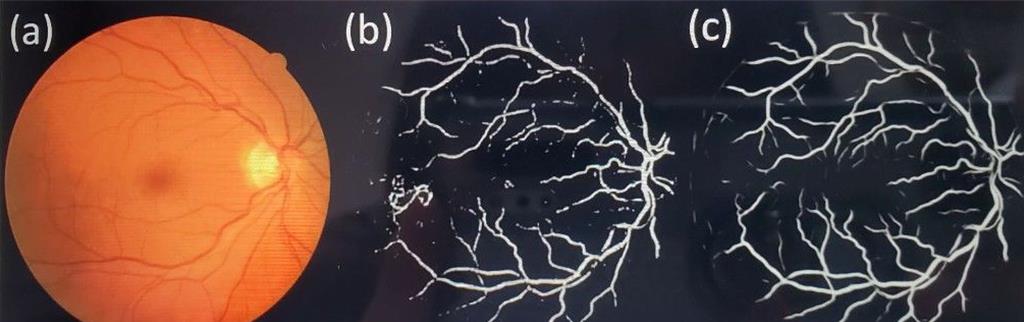

雲科大電子系特聘教授陳錫釗研發的人工智慧視網膜血管影像重建方法,圖左是眼球攝影影像,中間是傳統醫學手繪影像,圖左是AI繪製的影像。(陳錫釗提供)

特聘教授陳錫釗10多年前就研發出以皮膚紋路判讀年齡的技術,最近再研發出以人工智慧技術結合眼科,發明人工智慧視網膜血管影像重建方法,獲得2023年韓國首爾發明金牌獎,目前與台大雲林分院合作初探,只需2.6秒就可把眼球影像轉為血管構造圖,幫助醫師先期判讀視網膜血管病變。

陳錫釗對比AI深度學習繪製的圖檔,以及傳統醫學手繪的圖,AI繪製的時間只要2.6秒,準確率高達96%,可成功預測細小血管的結構。